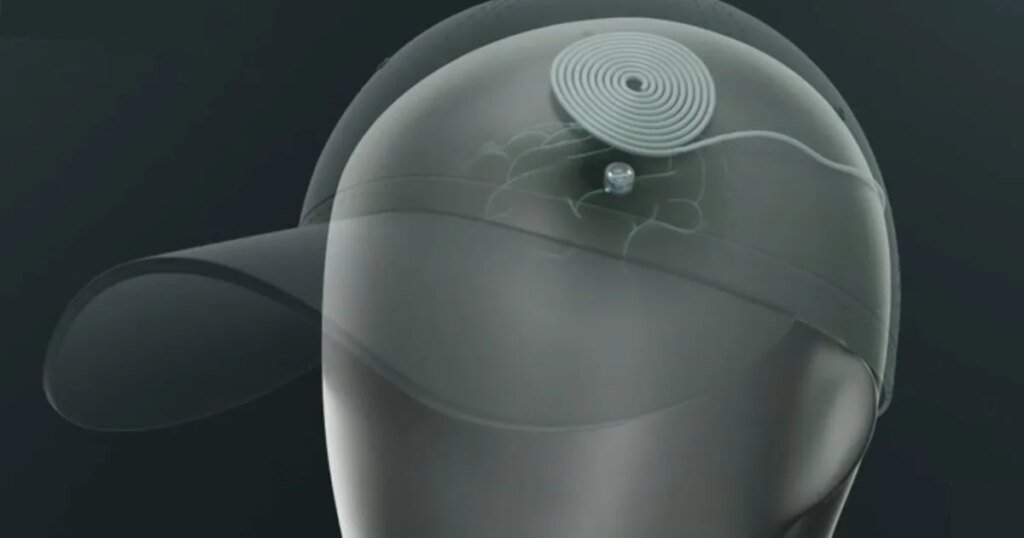

As soon as implanted, the gadget is powered wirelessly. Sufferers cost and management it utilizing a baseball cap that sends stimulation information on to the implant. You put on the cap for 10 to twenty minutes, a number of instances a day, and that’s your remedy.

Motif

Motif